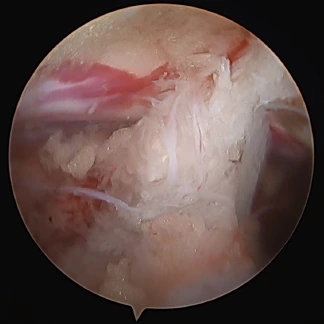

当院では、膝関節、肩関節(腱板修復術、バンカート修復術)、手指(手根管開放術)、股関節の疾患に対して「関節鏡視下手術」を行っています。関節鏡視下手術とは、まず手術をする関節の周囲に6~7mmの皮膚切開を数個作り、この小さな切開口から細いカメラ(内視鏡)や手術器具を関節内に入れて、モニターで内部を目視しながら行う手術のことです。関節鏡を用いる手術では、手術時の切開口が小さくて済むので、術後の回復が早いのが特徴です。体力的にも美容的観点からも患者さんの負担が小さいなどのメリットもあります。

UBE/BESS (Unilateral Biportal Endoscopy/Biportal Endoscopy Spine Surgery)の略称で、現在アジアを中心に脊椎手術の主流になりつつある術式です。従来の単孔式内視鏡下手術と大きく異なる点は、2孔式という点です。2か所小さく皮膚を切開し、片方から先端にカメラが付いた専用の内視鏡を挿入、もう一方から手術機器を挿入します。約5㎜と10㎜程度の小さい切開で済むため、背中の筋肉や組織の損傷を最小限に抑え、術後の痛みも軽くなります。

腰椎椎間板ヘルニアの術中画像